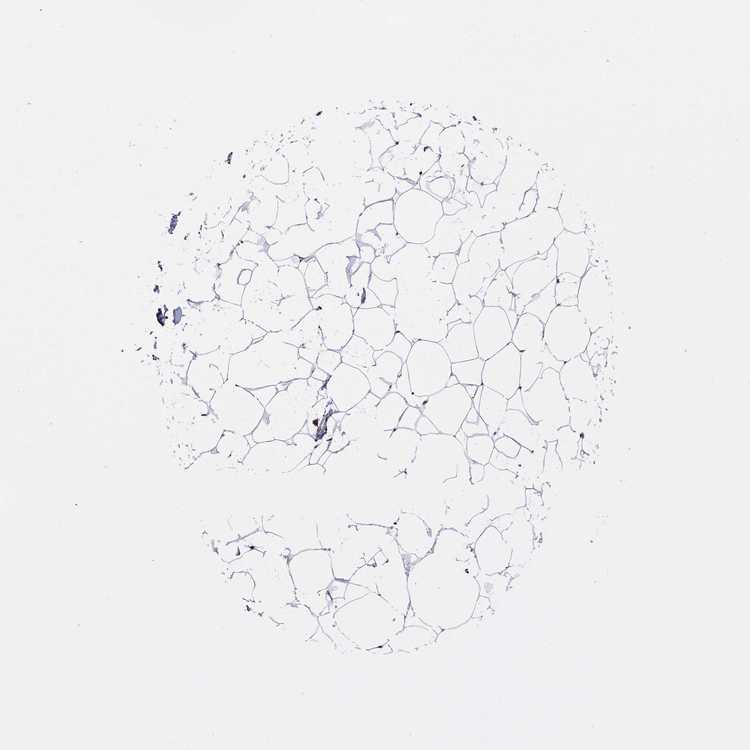

BREAST - Antibody stainingi

Antibody staining in the annotated cell types in the current human tissue is reported as not detected, low, medium, or high, based on conventional immunohistochemistry profiling in selected tissues. This score is based on the combination of the staining intensity and fraction of stained cells.

Each image is clickable and will lead to virtual microscopy that enables deeper exploration of all samples and also displays staining intensity scores, fraction scores and subcellular localization as well as patient and tissue information for each sample.

Antibody HPA068802

Adipocytes Medium

Glandular cells High

Myoepithelial cells High